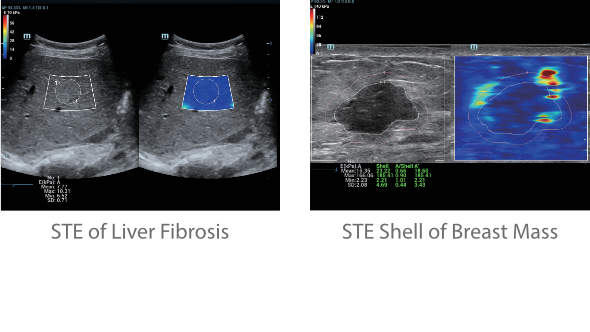

Desde que a empresa foi fundada, a Mindray est├Ī continuamente explorando novas maneiras de melhorar a confian?a no diagn├│stico. Alimentada pela mais revolucion├Īria tecnologia ZONE Sonography?, a nova plataforma Resona 7's ZST+ traz uma qualidade de imagem ultra-som a um n├Łvel superior por aquisi??o de zona e processamento de dados do canal.

Assim como o n├Łvel de qualidade de imagem premium, o Resona 7 tamb├®m melhora as capacidades de investiga??o cl├Łnica com o revolucion├Īrio Fluxo V para avalia??o hemodin?mica vascular e a aquisi??o de plano mais inteligente do conjunto de dados 3D para diagn├│stico CNS fetal. Combinando a opera??o mais intuitiva baseada em gesto de multi-toques e todos os recursos cl├Łnicos essenciais, Resona 7 est├Ī realmente conduzindo novas ondas na inova??o de ultra-som.